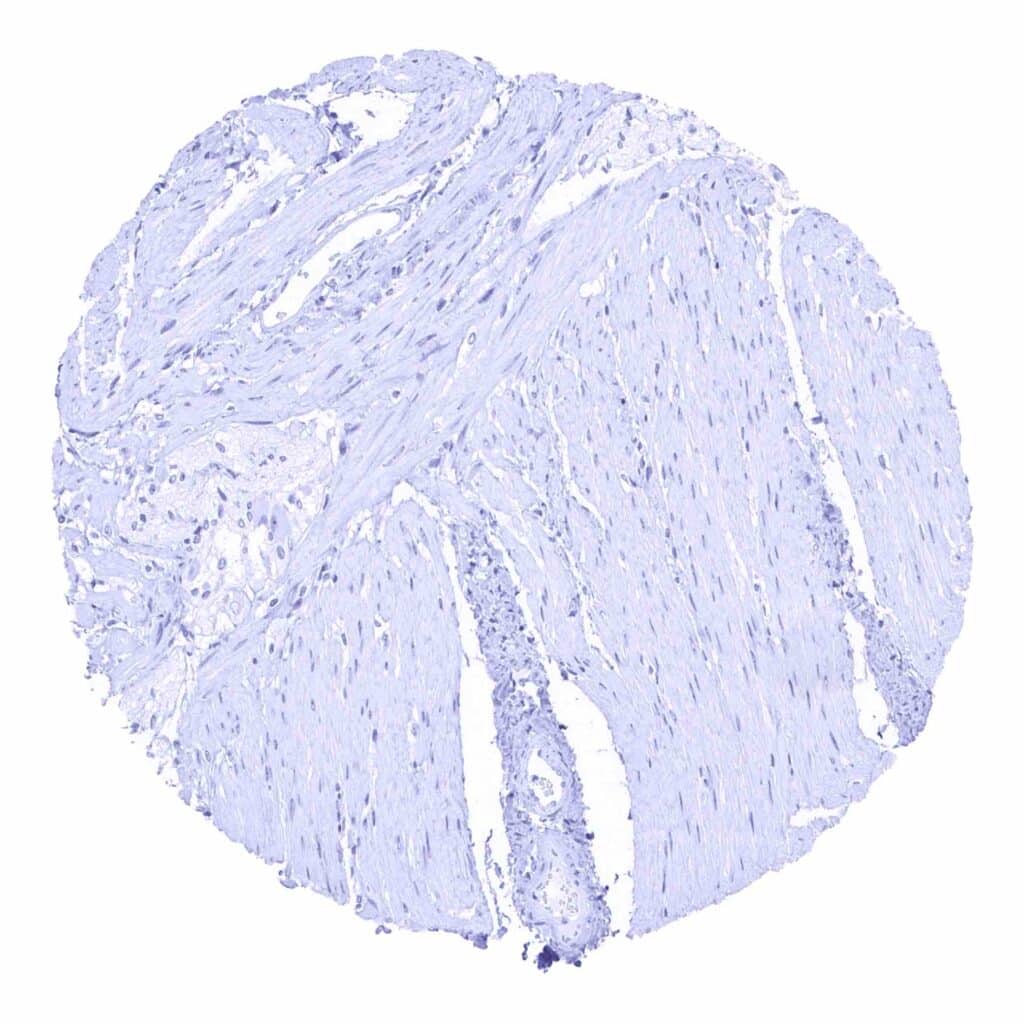

Uterus, myometrium